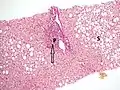

![]() | |

| Cross-section of human liver with cirrhosis | |

Once the biopsy is obtained, a pathologist will study the sample. Cirrhosis is defined by its features on microscopy: (1) the presence of regenerating nodules of hepatocytes and (2) the presence of fibrosis, or the deposition of connective tissue between these nodules. The pattern of fibrosis seen can depend on the underlying insult that led to cirrhosis. Fibrosis can also proliferate even if the underlying process that caused it has resolved or ceased. The fibrosis in cirrhosis can lead to destruction of other normal tissues in the liver: including the sinusoids, the space of Disse, and other vascular structures, which leads to altered resistance to blood flow in the liver, and portal hypertension.[82]

Macroscopically, the liver is initially enlarged, but with the progression of the disease, it becomes smaller. Its surface is irregular, the consistency is firm, and if associated with steatosis the color is yellow. Depending on the size of the nodules, there are three macroscopic types: micronodular, macronodular, and mixed cirrhosis. In the micronodular form (Laennec's cirrhosis or portal cirrhosis), regenerating nodules are under 3 mm. In macronodular cirrhosis (post-necrotic cirrhosis), the nodules are larger than 3 mm. Mixed cirrhosis consists of nodules of different sizes.[86]

Micronodular cirrhosis, with diffuse areas of pallor